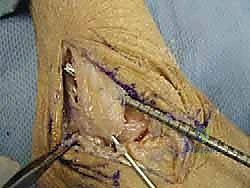

خطوات العملية الجراحية خطوة بخطوة مع الأستاذ الدكتور محمد هطيف

تتميز الجراحة في عيادة الدكتور هطيف بالدقة المتناهية واستخدام أحدث التقنيات العالمية. إليك كيف تتم العملية:

5. تثبيت الطعم:

يتم تمرير الطعم داخل الأنفاق العظمية وتثبيته بقوة باستخدام براغي تداخلية (Interference screws) مصنوعة من مواد تذوب حيوياً وتندمج مع العظم بمرور الوقت. يتم ضبط شد الطعم بدقة لضمان ثبات الكاحل مع الحفاظ على نطاق الحركة الطبيعي.

6. الإغلاق والجبيرة:

يتم إغلاق الشقوق الجراحية الصغيرة بغرز تجميلية، ثم يوضع الكاحل في جبيرة أو حذاء طبي واقٍ لحماية الأربطة الجديدة أثناء بدء مرحلة الالتئام.